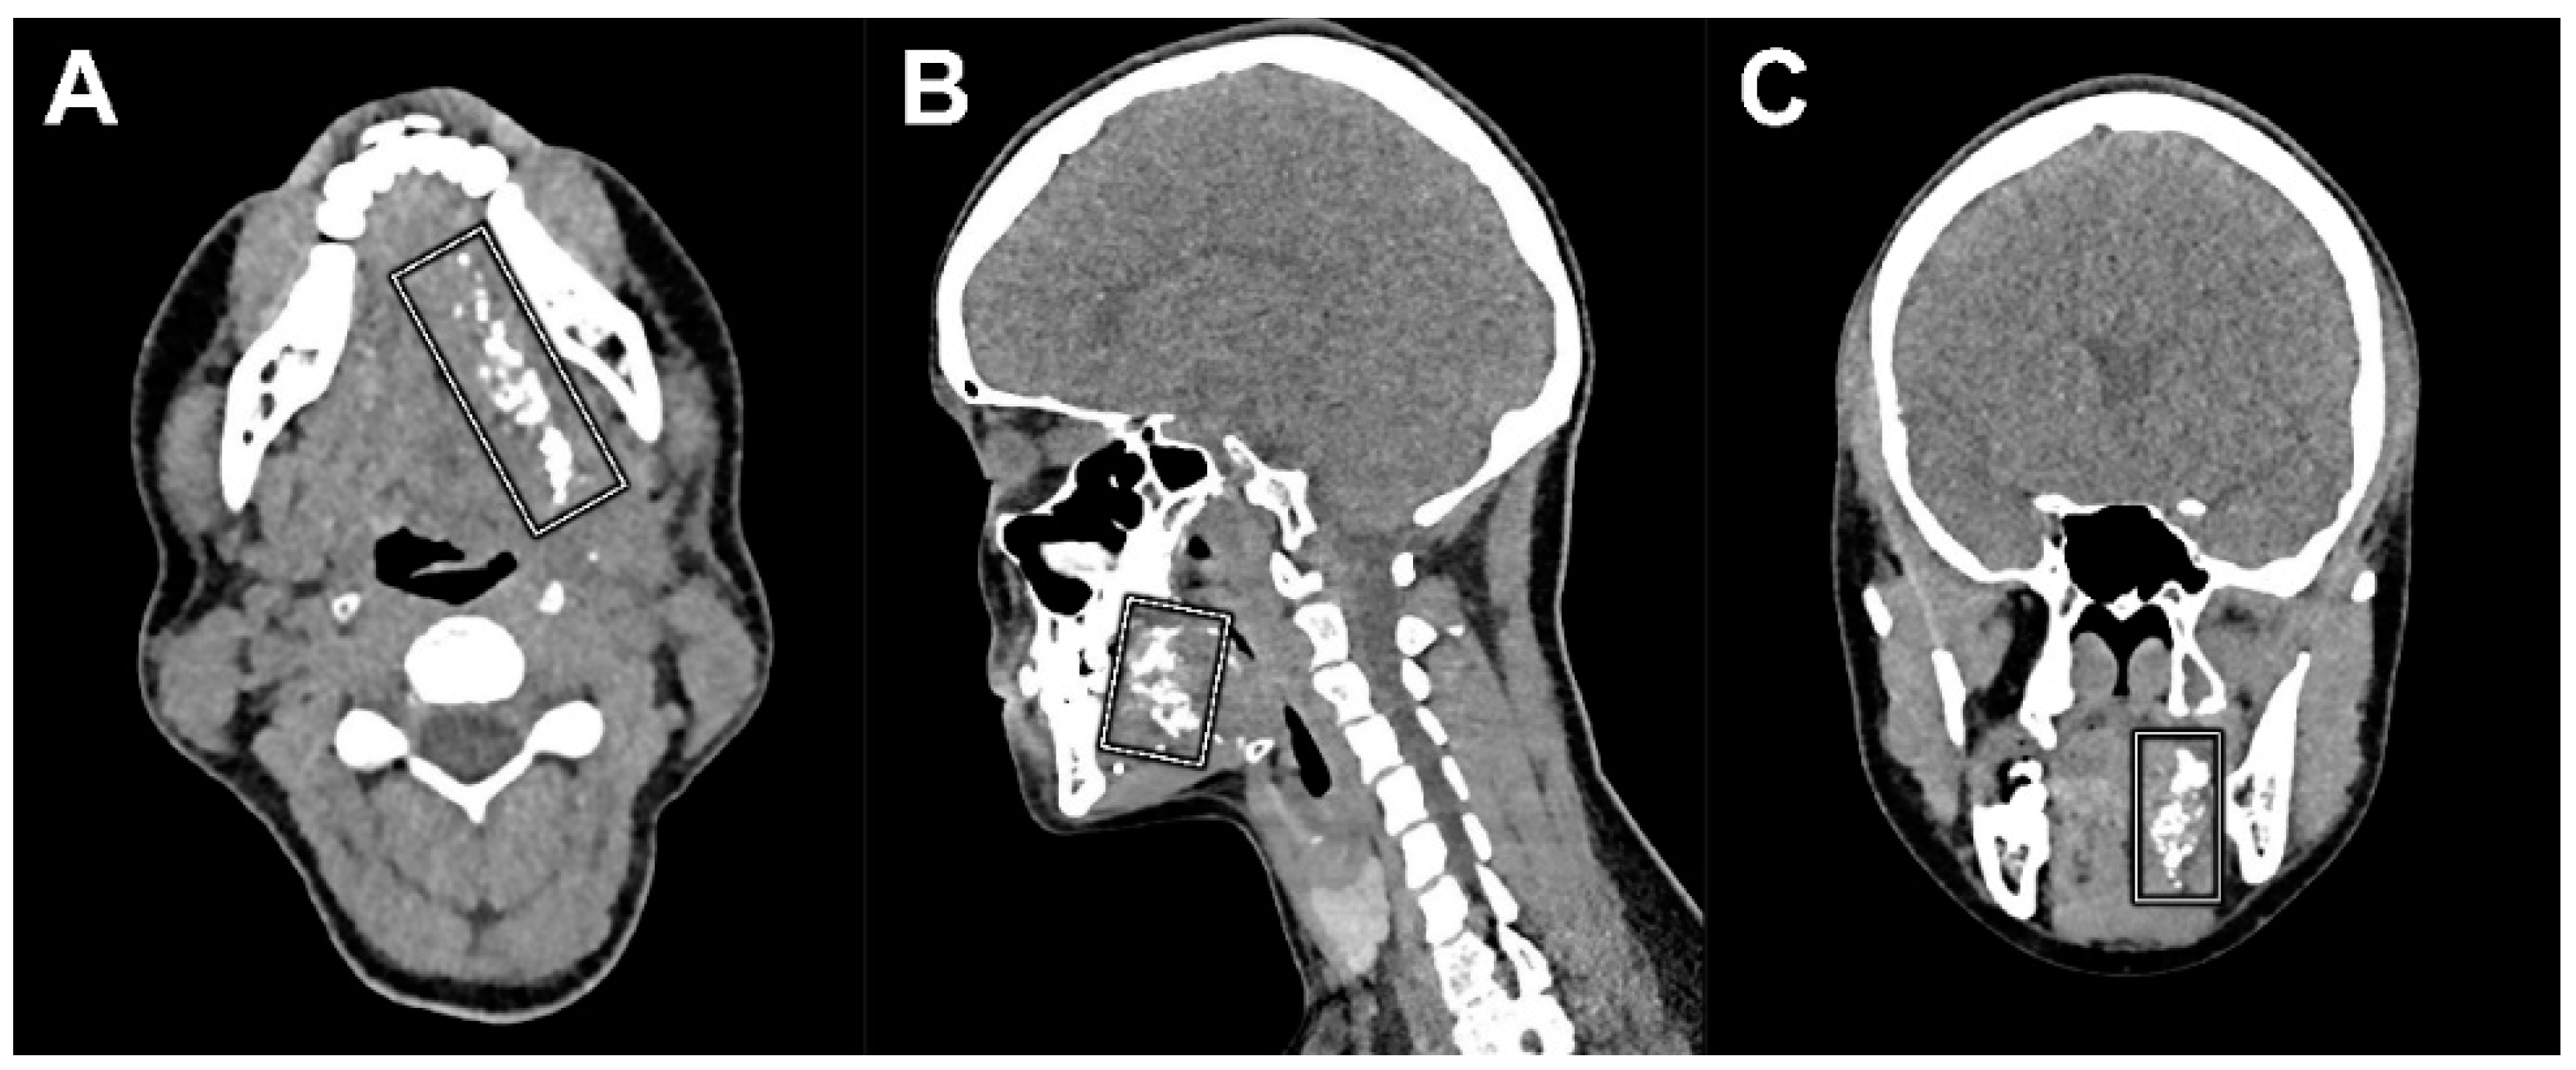

Figure 6.

CT images as part of the FDG-PET/CT acquired 13 days following peritumoral administration of Lipiodol® (patient 6) clearly depicts remains of Lipiodol® located around the initial primary tumor site (white squares). (A) Axial plane, (B) coronal plane, and (C) sagittal plane.